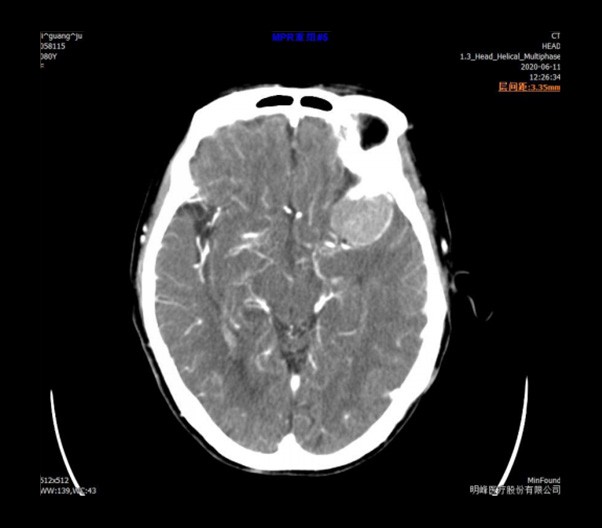

ScintCare Blue 755 incorporates an entirely digital integrated ScintiStar detector, which was solely developed by MinFound, from material to the whole structure design, based on the technical know-how of our skilled scientific team. The system produces high-resolution images with a low radiation dose and an excellent signal-to-noise ratio.

NDI NanoDose iteration algorithm is an innovative iterative technique for image reconstruction that takes full advantage of deep learning in anatomical structure in image space as well as model-driven iteration involving tube and detector in projection space, with the aim to generate sharp images in high resolution at the lowest possible dose.

臨床畫廊